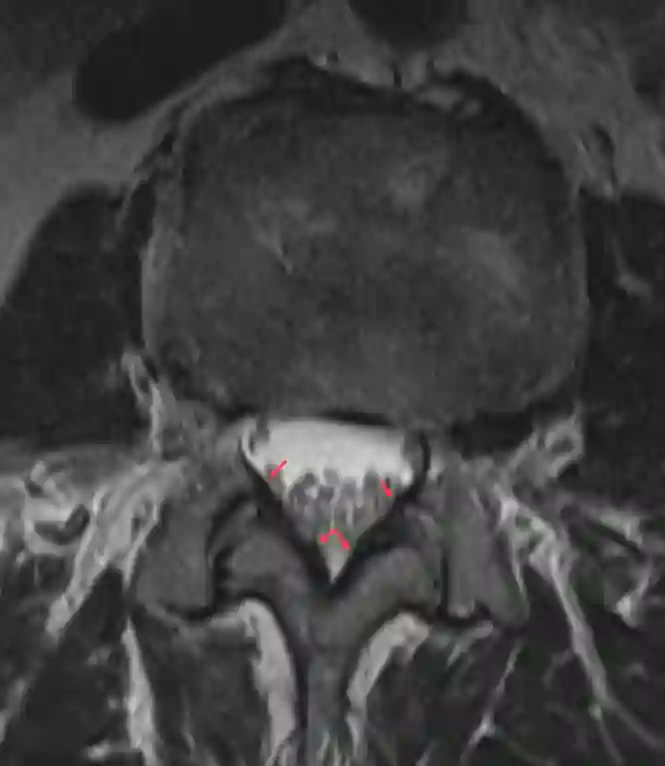

Ligamentum flavum im MRI

Darstellung des Ligamentum flavums im axialen MRI Bild der lumbalen Wirbelsäule.